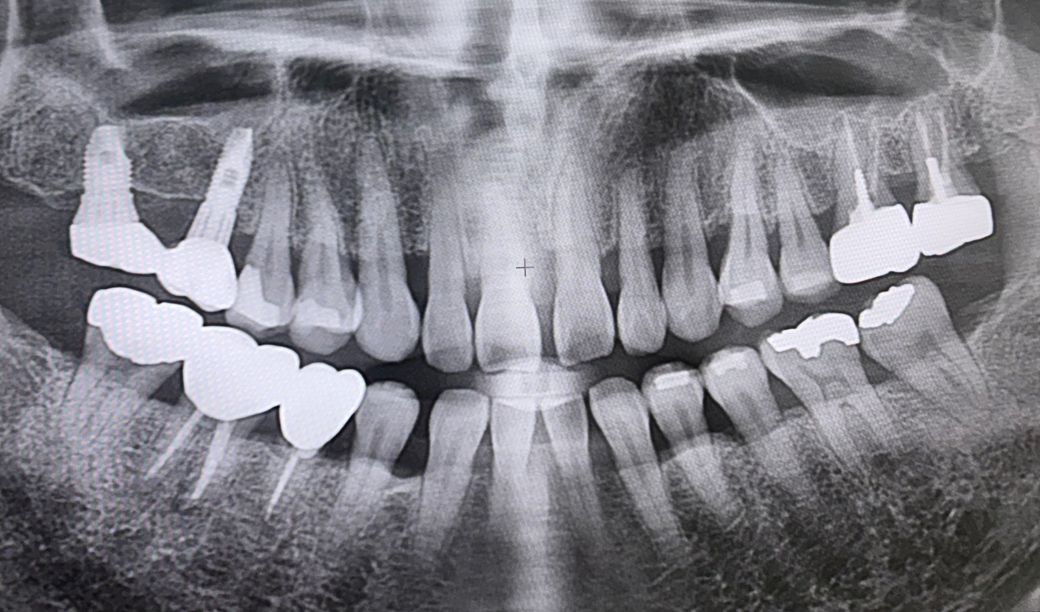

차례로 24년 8월 엑스레이와

사진상 왼쪽 신경치료된 어금니가

저작시는 괜찮은데 옆으로 뉴르면 미세하게

아파요.

위로 누르면 안아파요

치과를 가봐도 신경치료 잘됐고(2-3년됨)

큰 이상 없대는데 ㅠㅠ

• 1번 째 사진